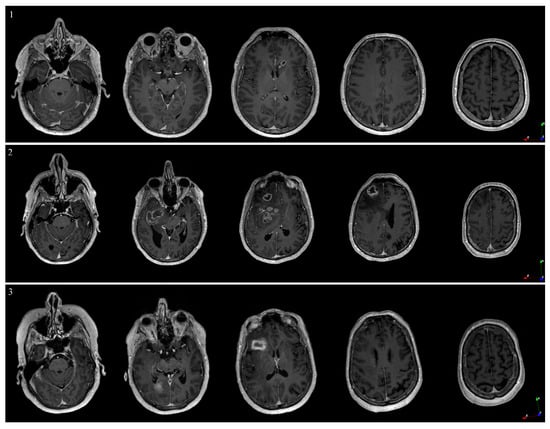

3.3. Patient Cases

| Patient | |||

|---|---|---|---|

| Parameter | 1 | 2 | 3 |

| Image Acquisition | |||

| Reference space | MR DICOM | CT | MR DICOM |

| Pixel spacing [mm] | 1 × 1 × 1 | 1 × 0.977 × 0.977 | 1 × 1 × 1 |

| Field of view [mm] | 192 × 256 × 256 | 176 × 256 × 256 | 176 × 256 × 256 |

| Acquisition time [min] | 21 | 21 | 21 |

| Postoperative image type | CT | CT | MR |

| Neuronavigation Errors | |||

| Registration [mm] | 1.9 | 1.5 | 1.6 |

| Targeting [mm] | 0.1 | 0.2 | 0.5 |

| Time | |||

| Optical measurement [min] | 7 | 7 | 9 |

| Intraop diagnosis [min] | 50 | 60 | 60 |

| Final Diagnosis | |||

| CNS WHO 2021 | High-grade astrocytoma, IDH-wildtype | Glioblastoma, IDH-wildtype, grade 4 | Primary diffuse large B-cell lymphoma of the CNS |

| Analysis (pre- vs. postop) | |||

| Euclidian distance [mm] | 3.1 ± 0.48 | 3.3 ± 1.2 | 1.3 ± 0.25 |